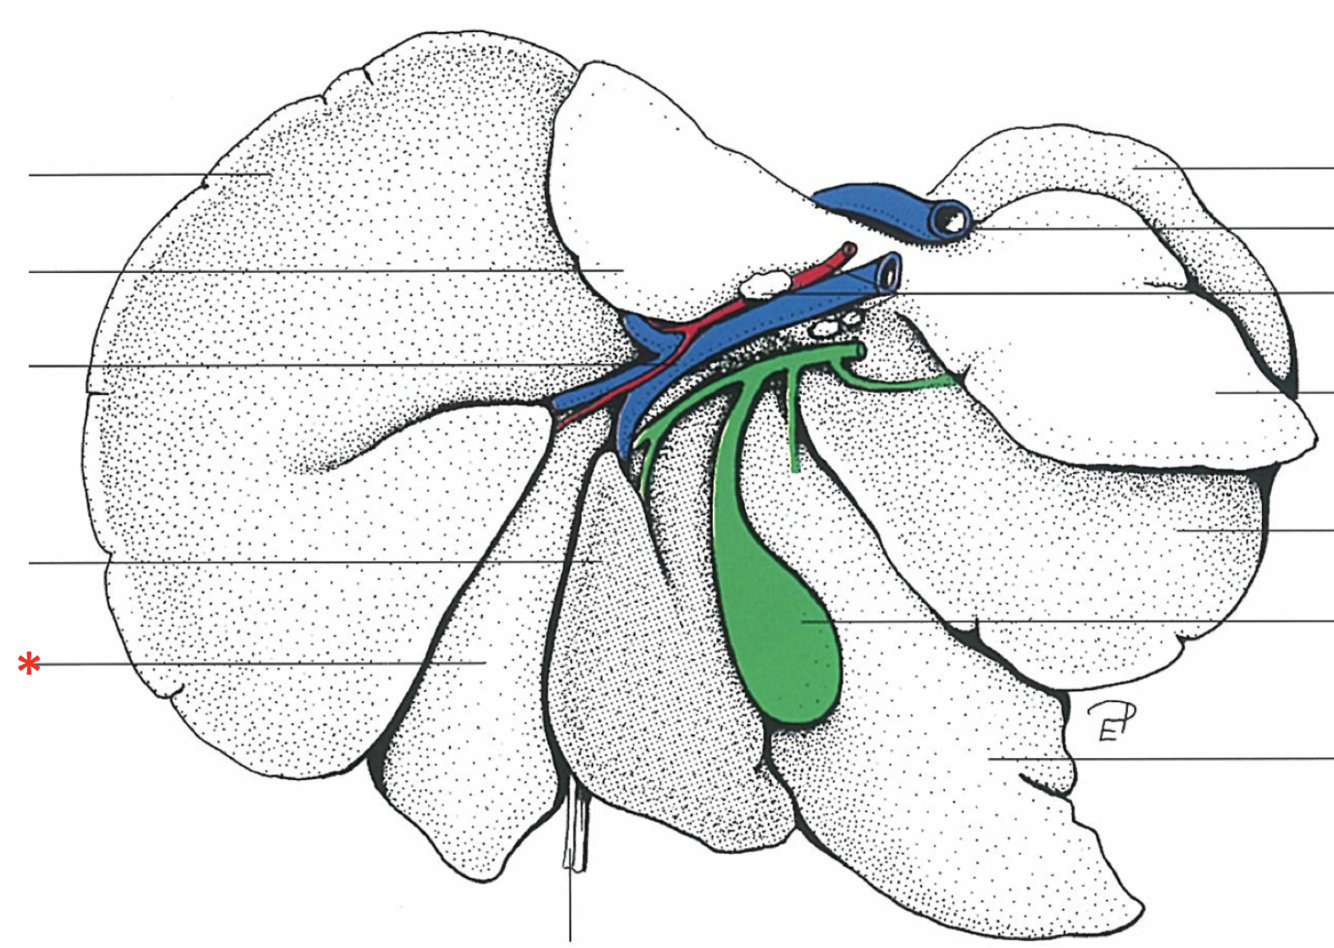

Dorsal Aspect

Area nuda

- Not covered by serous membrane

The Caudate Process extends from the…

Lobus caudatus

The sharp-edged border of the liver is called…

Margo acutus

The blunt-edged border of the liver is called…

Margo obtusus

Ligg.falciformehepatiset tereshepatis

18

Lig. coronale hepatis

15

Lig. hepatogastrica

16

Lig. hepatoduodenalis

- Adjacent to ostium pyloricum

Lig. triangulare sinistrum

Lig. triangulare dextrum

Lig. hepatorenale